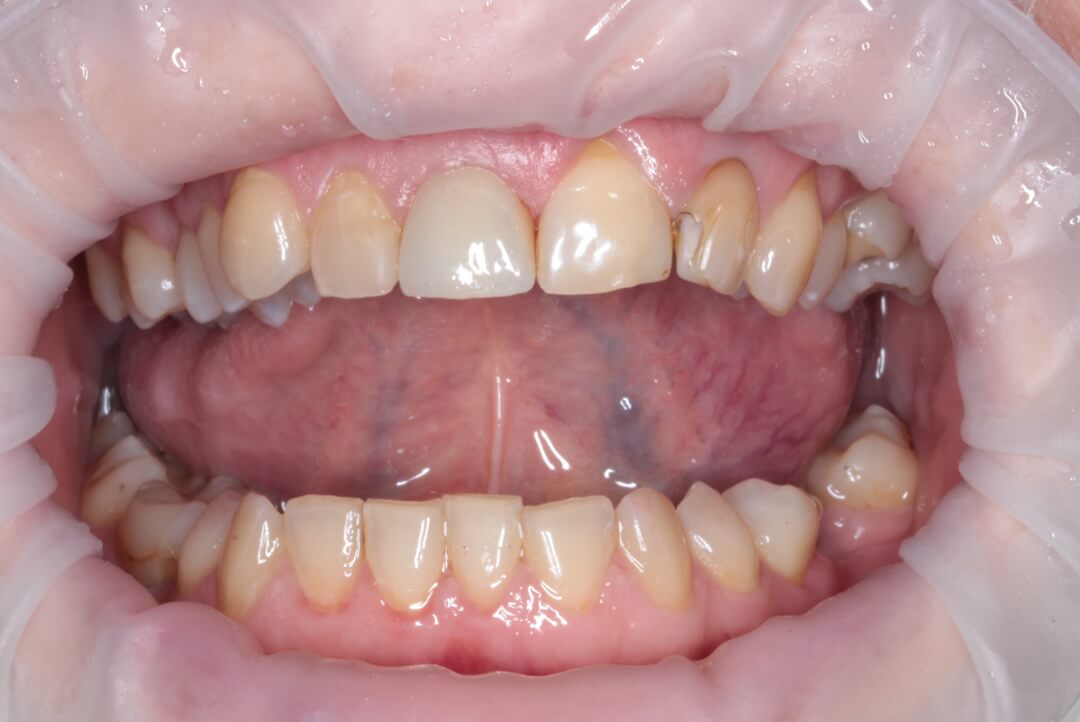

Зуб был атравматически удален фрагментированием на части с помощью пьезохирургического аппарата и элеватора для максимального сохранения объема костной ткани в месте будущей дентальной имплантации. Во время экстракции врач сохранил целостность вестибулярной стенки альвеолы. Восстановление дефекта мягких тканей в данной области проводилось при помощи туннельной технологии субэпителиальным небным десневым трансплантатом . Устранение дефекта слизистой оболочки и десен способствует стабильному высокоэстетическому результату лечения. После этого хирург осуществляет наращивание костной ткани в вестибулярной области с использованием твердых частиц остеопластического материала. Для предотвращения попадания костного материала на внутреннюю часть имплантата врач устанавливает формирователь десны. Учитывая то, что пациентка по профессии учитель и впереди у нее было много ответственных мероприятий, было принято решение изготовить временную коронку на дентальный имплант непосредственно во время операции, так как все необходимые для этого условия были соблюдены и была такая возможность для этого.

Рис. 2. Вид пациентки после всех проведенных манипуляций в первое посещение.